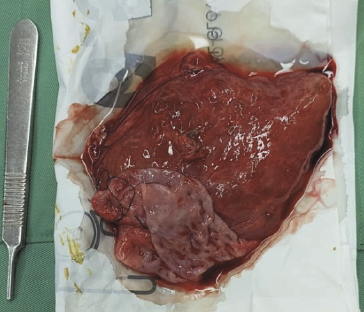

It was determined by anamnesis, physical examination, and imaging that the diagnosis was an ovarian cyst. As we continue laparotomy with midline incision from obstetrics department, we revealed a 8x8x10 cm sized cystic mass within the left transverse colon omentum, uterus and both ovaries were normal (Figure 3). We excised the cyst in toto and omentectomy then sent for pathological anatomy and cytology analysis. Instead of an ovarian cyst, we found an omental cyst during the operation (Figure 4), thus we had to conduct an excision and omentectomy and postoperatively achieved favorable results. Pathological examination revealed findings a inclusion cyst containing connective tissue, fat, and muscle. Cytology findings are suggestive for transudative effusion from the cyst and the international system for reporting serous fluid (ascites) cytopathology negative for malignancy (Figure 5). She was discharged three day after.

Figure 4. Cut-open omental cyst